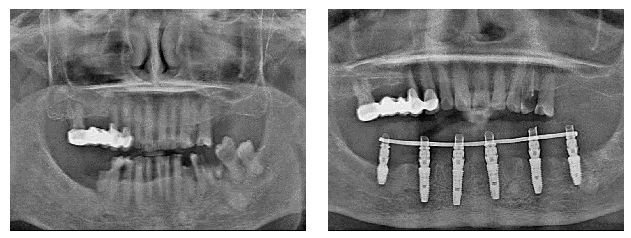

1、即刻种植,植入4至6颗种植体,当天种牙,当天戴牙,当天就能用;

2、缺骨种牙,无需植骨,严重牙槽骨萎缩、骨质疏松、糖尿病及高龄人群福音;

3、咀嚼力95%,稳定性强、可长期使用,缩短治疗周期,成功案例6000+。

All-on-4(6)优势

1、即刻种植,无需等待几个月,当天种好一口牙;

2、即刻修复,即刻戴上固定义齿,牙齿不脱好开心;

3、即刻负重,当天手术当天恢复咀嚼功能,尽情享用美食;

4、个性定制,量身定制种植,只种最适合自己的牙;

5、微创基本无痛,无需植骨即可种植,手术很轻松;

6、数字化美学中心,3D扫描、取片、建模等,精确分析口腔微环境。